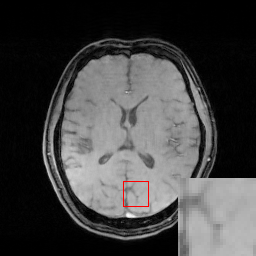

We evaluate the proposed DECN framework using PSNR and SSIM (structural similarity index) [30] as quantitative image quality assessment measures. We give the quantitative reconstruction results of all the test data on different under-sampling patterns and different under-sampling ratios in Table II. We show the Cartesian 30%percent3030\% under-sampling mask in Figure 6(b) and the Random 20%percent2020\% under-sampling mask in Figure 7(b). We observe that DECN improved all off-the-shelf CS-MRI inversion methods on all the under-sampling patterns. Since the Random mask enjoys the more incoherence than the Cartesian mask with the same under-sampling ratio, the CS-MRI achieves better reconstruction quality on the Random masks. Also, we observe the plain DC-CNN model already achieves good reconstruction accuracy, leaving less structural errors for the error correction module, leading to the limited performance improvement about 0.1 dB on the Random 20%percent2020\% and 30%percent3030\% masks. While for other CS-MRI inversions on various sampling patterns, the improvements are at least 1.5dB or even up to 3.5 dB.

In Figure 7, we also compare the MR images produced by the TLMRI, PANO and GBRWT with their DECN counterparts on the 2D 20%percent2020\% under-sampling mask. The subjective comparison DC-CNN and DE-CNN-DECN isn’t included because of the limited improvement. The results are consistent with our observation in Cartesian under-sampling case.